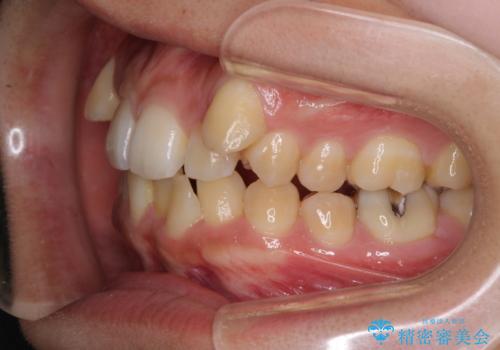

八重歯の抜歯矯正 補助装置を用いたインビザライン矯正

- 下の前歯のデコボコを気にして来院された患者様です。

来院当初、上顎の八重歯は気にしていらっしゃらなかったのですが、矯正治療をするのであれば、しっかりと治した方が良いと説明し、全顎矯正を行うこととしました。

装着時間をしっかりと守ってくださったので、予定通りの期間で終了することができました。